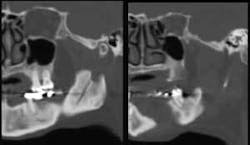

Upon examination, I noted exposure of the mandible on the lingual running from Teeth Nos. 18 and 19. At that time there was no information available to suggest treatment of this problem, and the patient and I agreed to monitor the situation.

She was immediately referred to an oral surgeon. Upon examination he discovered mandibular necrosis around Tooth No. 31. The situation had become life-threatening, as the infection was now out of control and spreading through the soft tissue, floor of the mouth, and buccal space.

After much discussion, the patient and her husband agreed to extraction of No. 31 knowing that necrosis of the right mandible would probably occur. The patient was admitted to the hospital for incision and drainage of the lower right mandible and extraction of No. 31.

At the two-month evaluation, we were pleased to see healing and gingival closure of the extraction site.